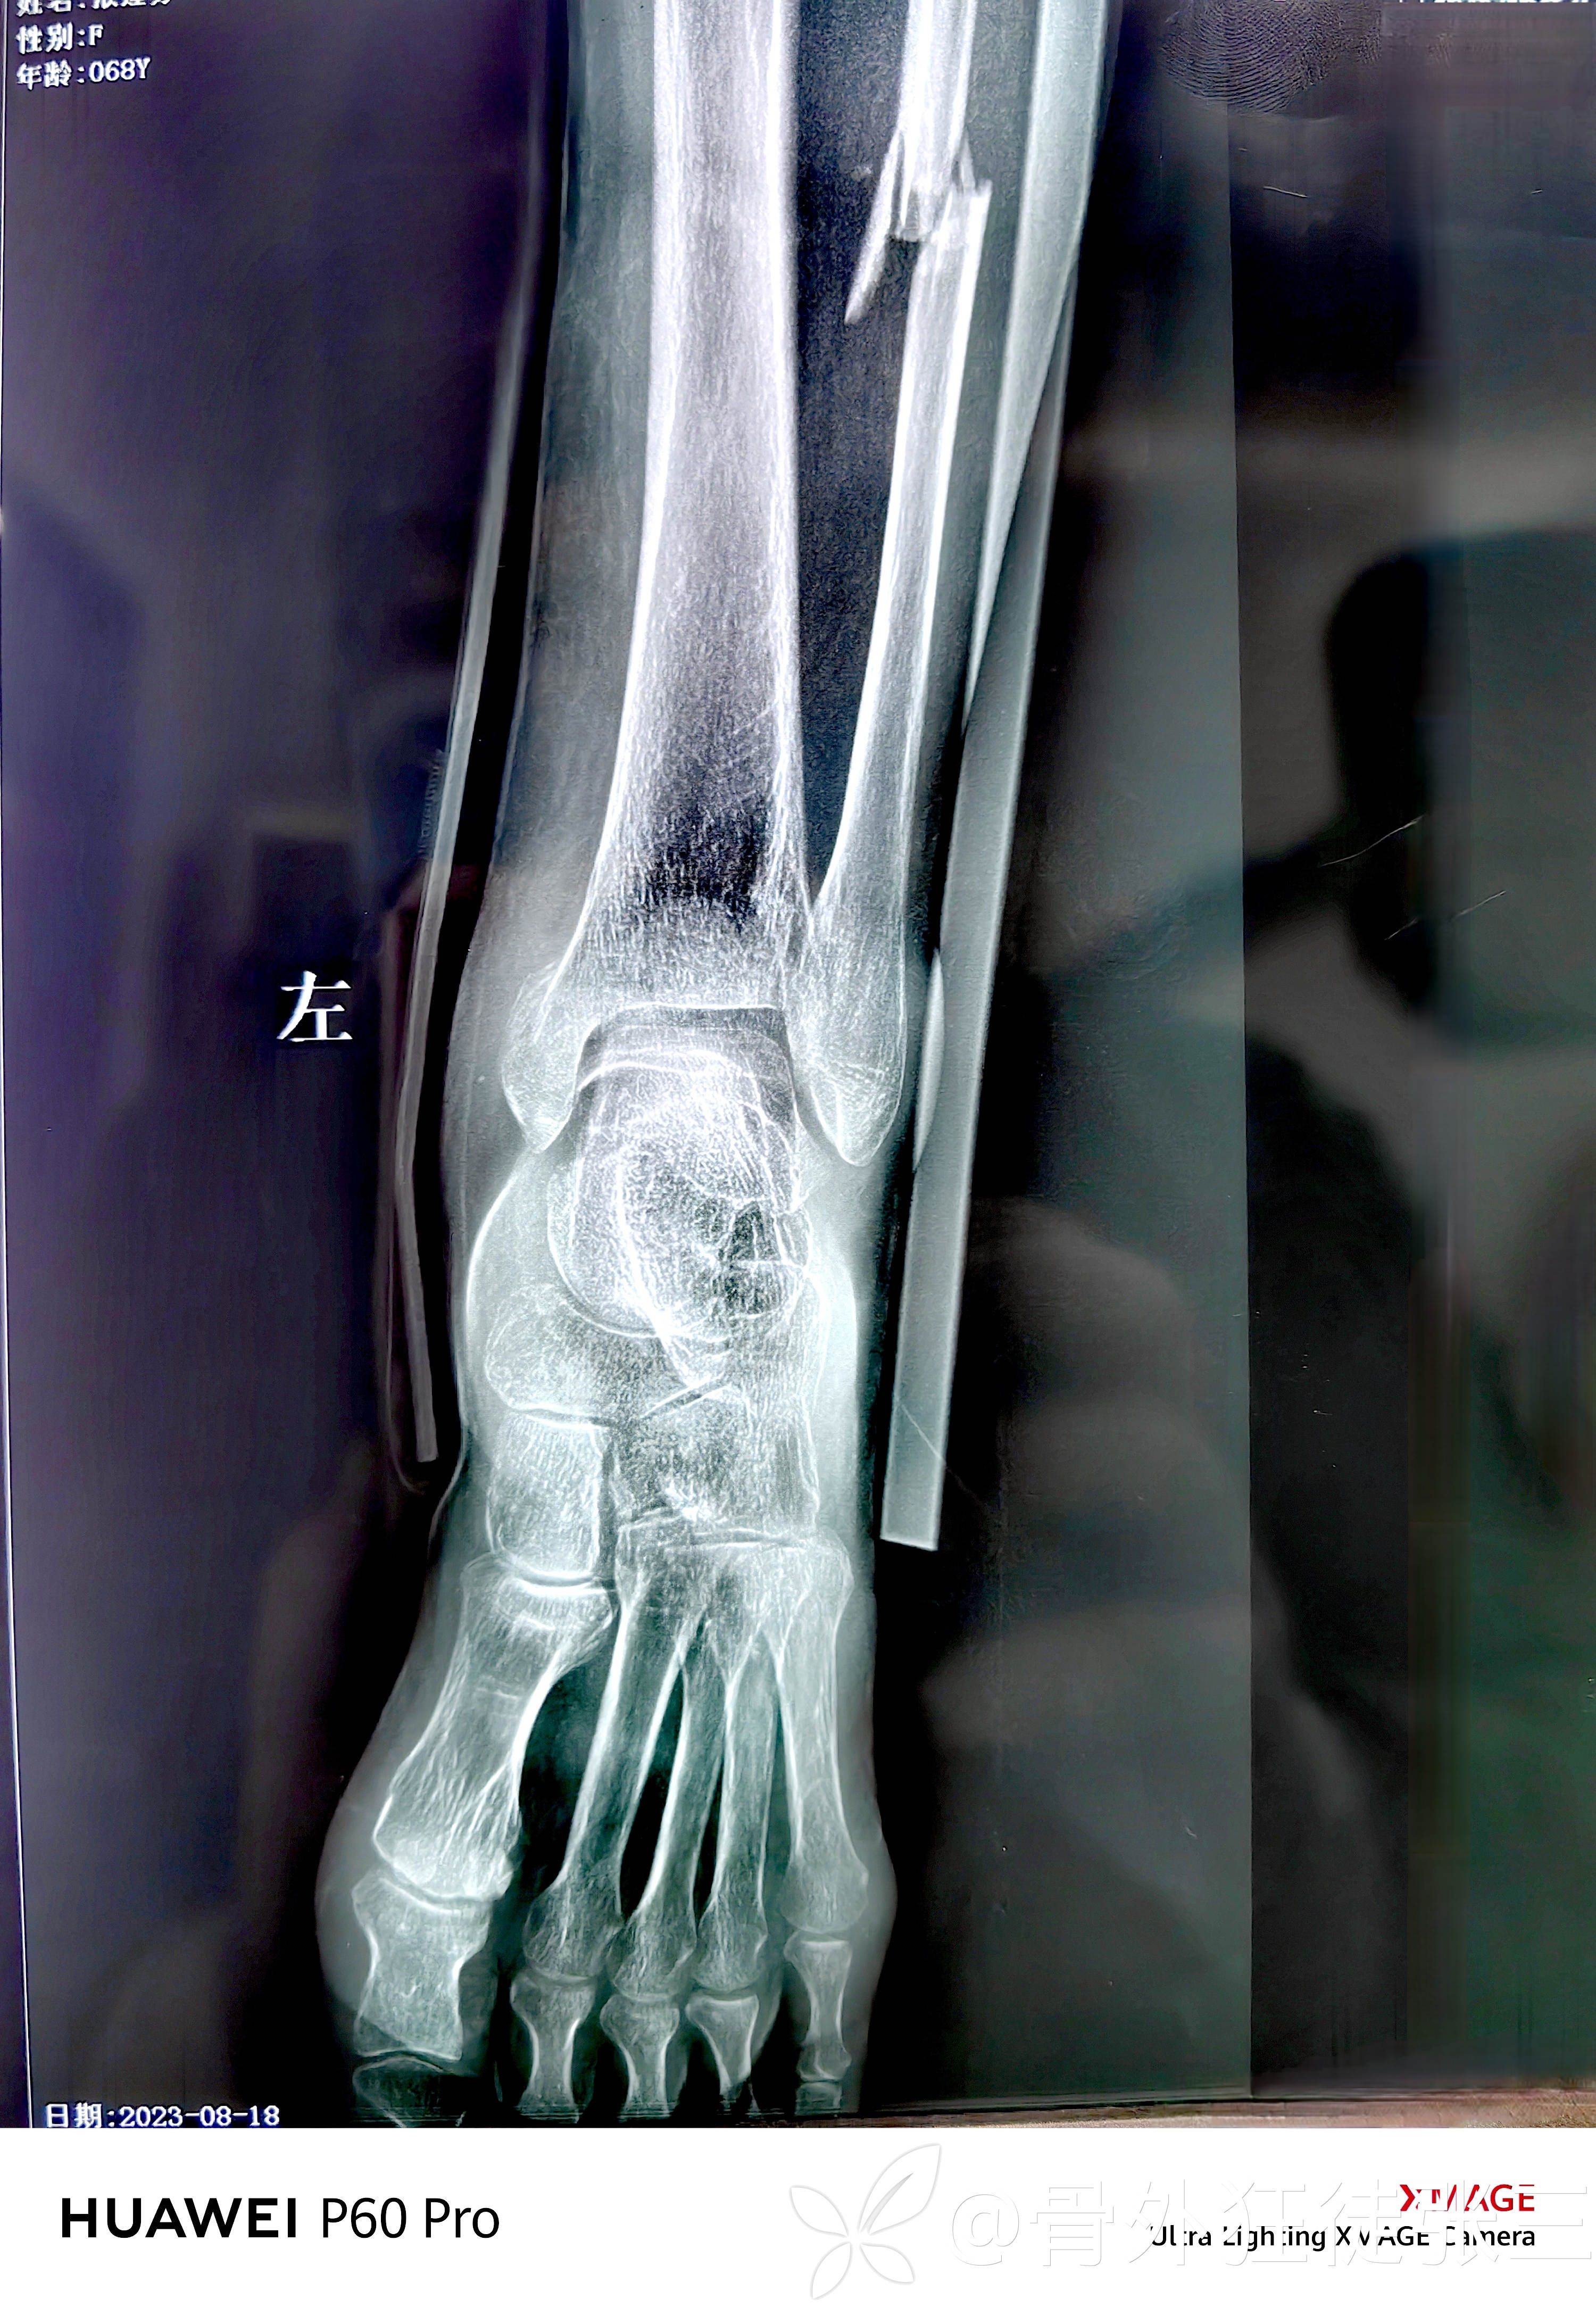

旋前外旋四期踝关节骨折脱位一例

患者性别:女

患者年龄:68岁

主诉:车祸致左踝关节疼痛、畸形、活动受限3小时。

辅助检查:

高位腓骨粉碎性骨折

内踝+后踝骨折

下胫腓分离

内踝骨折,胫距关节脱位